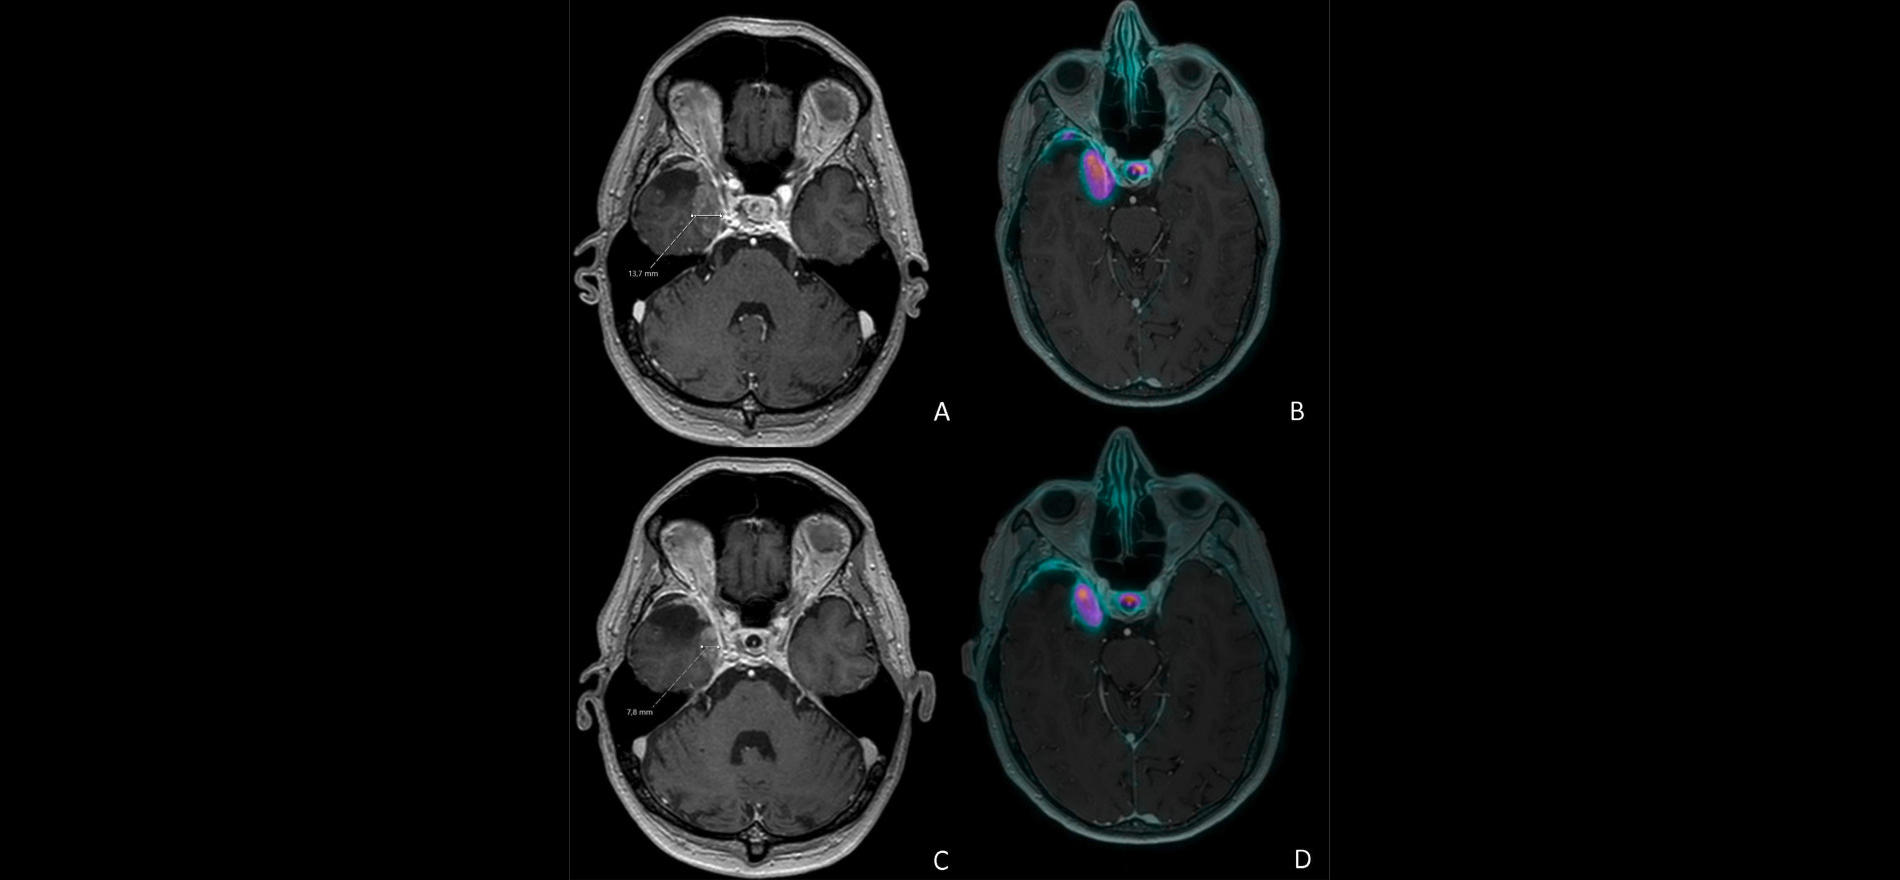

L’essai LUMEN-1, conduit par l’organisation pour la recherche et le traitement du cancer, a pour mission de remédier à cette lacune. Il vise à randomiser 136 patients atteints de méningiome de grade 1 à 3 en deux bras. Ceux du premier groupe recevront un traitement au [177Lu]Lu-DOTATATE (jusqu’à 4 doses de 7,4 GBq toutes les 4 semaines ; les autres bénéficieront du traitement médicamenteux standard ou d’une simple surveillance). Les participants d